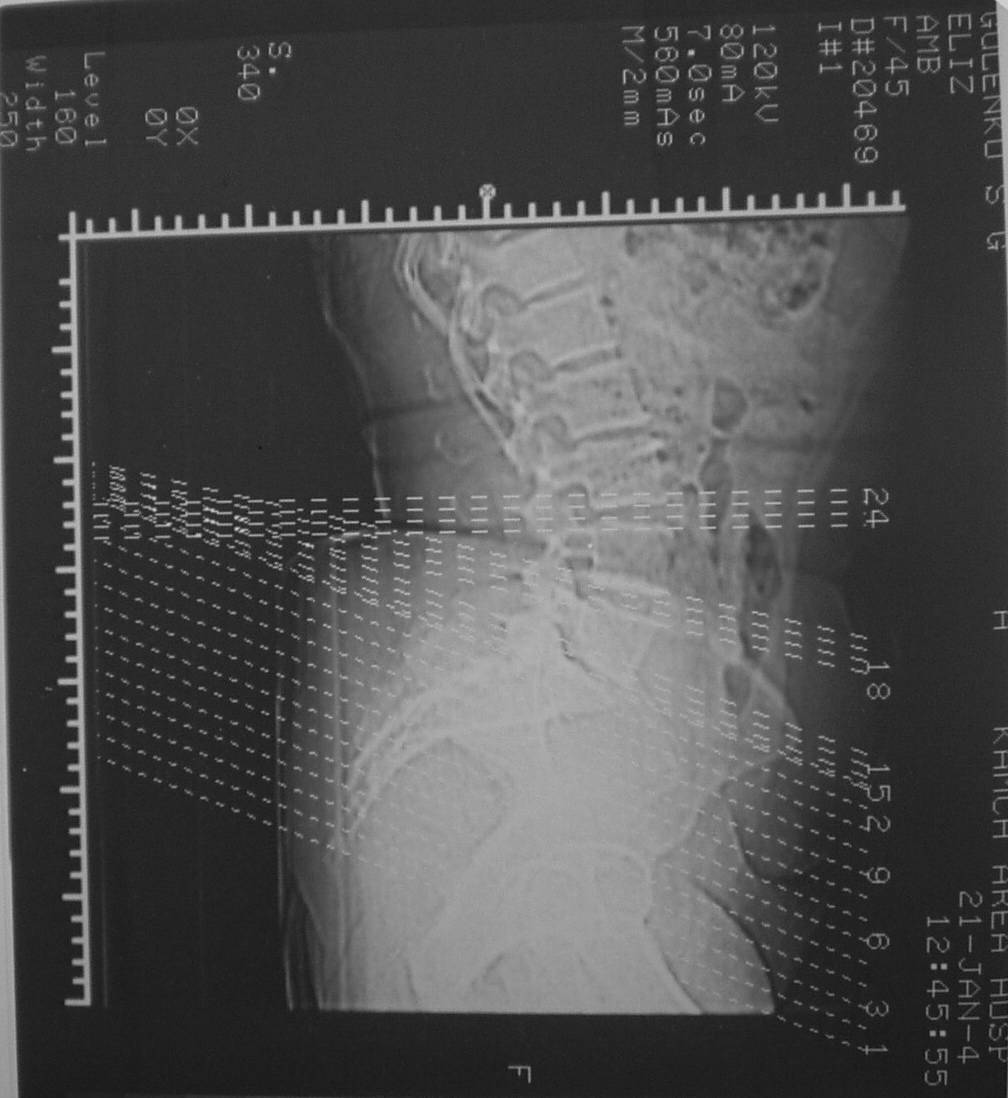

Уважаемые коллеги! Хотел-бы обсудить интерессный, на мой взгляд, случай.На консультацию пришла женщина 45 лет с отводящей контрактурой правого бедра.

Из анамнеза: в ноябре 2002г. оступилась,упалана трап самолета (на верхней площадке, сразу при выходе из салона) на правый тазобедренный сустав, а затем - вниз на землю на ноги и ягодицы. Потеряла сознание от боли. Доставлена в больницу по месту жительства, лечилась консервативно с диагнозом кокцигодиния.На рентгенограмме от 27.11.02г. вывиха копчика не определяется (снимок идентичен представленной R-грамме от28.11.03г., кроме этого есть нормальная R-грамма копчика в боковой проекции).Через три недели стала ходить, но привести правую ногу в тазобедренном суставе не могла. Сейчас ходит отведя кнаружи правое бедро и голень, как ножку циркуля (фото 1). Неврологических нарушений нет. По просьбе врачаможет на 30-40 секунд поставить ноги вместе (фото 2). При этом испытывает сильную тянущую боль и ощущение "вывернутости" в правом тазобедренном суставе. Эти ощущения заставляют вновь отвести бедро. В положении лежа разогнуть бедро полностью не может из-за болей в ягодичной мышце (фото 3). Сгибание также ограничено из-за болей (фото 4). Отведение в положении лежа возможно в том же объеме, что и стоя (фото 5). Заподозрен старый разрыв правого крестцово-подвздошного сочленения.Выполнено R-исследование и КТ(в приложении). По-поводу деформации лонного сочленения выяснен гинекологический анамнез. Роды одни, нормальные в 22 года. Из роддома выписана на 8 сутки, нарушения походки не было, R-графия таза не проводилась. Вопросы на обсуждение: 1. Диагноз либо алгоритм дальнейшего обследования. 2. Лечебная тактика (в первую очередь возможность и целесообразность оперативного лечения).